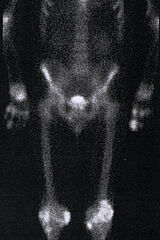

Nach Injektion eines knochenspezifischen Radiopharmakons kann das gesamte Skelett dargestellt, vor allem aber krankhafte Veränderungen im Bereich des Knochens und der Gelenke erkannt werden. Viele Erkrankungen führen zu einem verstärkten Knochenumbau, der als Region vermehrter Speicherung im Szintigramm sichtbar wird. So führen z.B. Entzündungen, Tumoren, Metastasen und Kallusbildung nach Frakturen zu sichtbaren Veränderungen im Szintigramm. Auch Gelenksentzündungen sind durch Aktivierung des an den Knorpel angrenzenden Knochens gut sichtbar.

Daraus ergeben sich folgende Hauptindikationen:

Die beste Darstellung des Skelettes gelingt ca. 3 Stunden nach Injektion, die Aufnahmedauer beträgt ca. 15 Minuten. Bei der Frage nach Entzündungen oder Durchblutungsstörungen des Knochens sind zusätzliche Aufnahmen unmittelbar nach Injektion erforderlich.